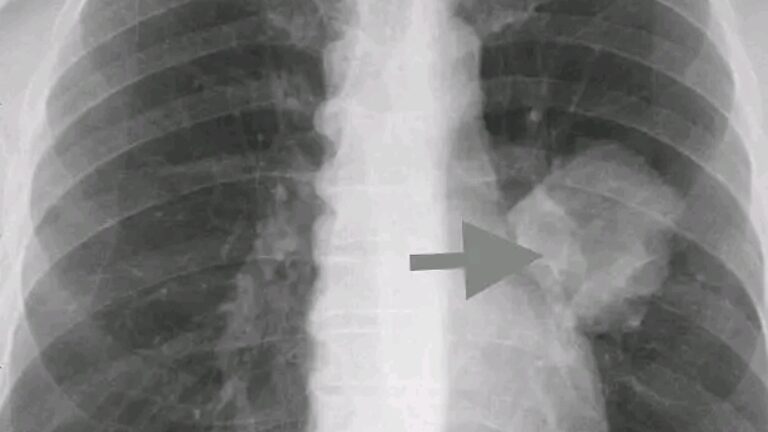

COVID 19. Alerta mundial

COVID 19. Alerta mundial vacunados

UltimaHora_COVID_19 Alerta Mundial para